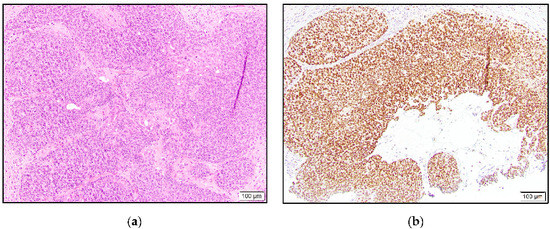

In the benign category, eight hidradenoma cases were intermediate to high positive, one was low positive, and two were negative. Similar to the eccrine adenocarcinoma case, four hidradenomas showed stronger staining in the cells lining cystic or ductular spaces (Figure 4).

Figure 4.

Hidradenoma with solid and cystic areas composed of eosinophilic cells and focal clear cells (a) and TRPS1 expression with accentuated staining in cells lining cystic spaces (b).

In the poroma group, six and two cases demonstrated intermediate to high and low positivity, respectively (Figure 5). One poroma was negative for TRPS1 expression. In the majority of the positive cases, variable staining intensity was present in the tumor cells. This finding was more evident in the hidradenomas.